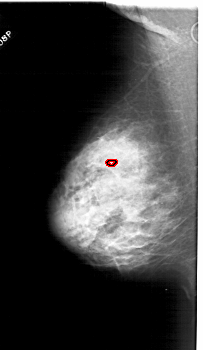

A_1803_1.RIGHT_MLO

RIGHT_CC LINES 5641 PIXELS_PER_LINE 3061 BITS_PER_PIXEL 12 RESOLUTION 43.5 NON_OVERLAY

FILE: A_1803_1.LEFT_MLO.OVERLAY

TOTAL_ABNORMALITIES 1

ABNORMALITY 1

LESION_TYPE CALCIFICATION TYPE PLEOMORPHIC DISTRIBUTION CLUSTERED

ASSESSMENT 4

SUBTLETY 2

PATHOLOGY BENIGN

TOTAL_OUTLINES 1